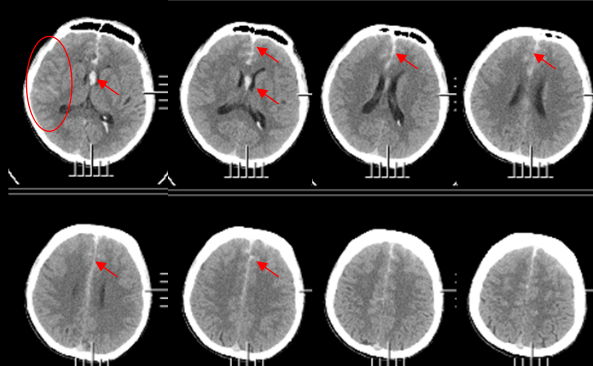

门诊头部CT显示双侧半球广泛蛛网膜下腔出血,进一步核磁检查显示:右侧大脑前动脉A2段动脉瘤,形态不规则。

入院头颅CT显示双侧蛛网膜下腔、纵裂、基底池脑室广泛出血